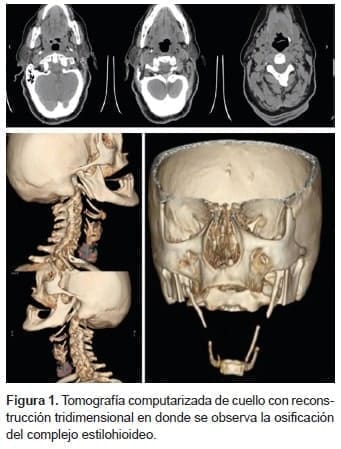

En una nueva tomografía computadorizada de cuello con reconstrucción tridimensional, se

observó una apófisis accesoria en el lado izquierdo del hioides, así como elongación de la apófisis estiloides derecha y ausencia posquirúrgica de la izquierda. Sin embargo, existía la posibilidad de que el asta accesoria del hioides correspondiera a la osificación caudal del ligamento estilohioideo (figura 1).

Para llegar a su diagnóstico, se debe tener un alto grado de sospecha y se confirma con una tomografía de cuello con reconstrucción tridimensional. Su tratamiento es quirúrgico, aunque también se ha descrito el manejo médico.